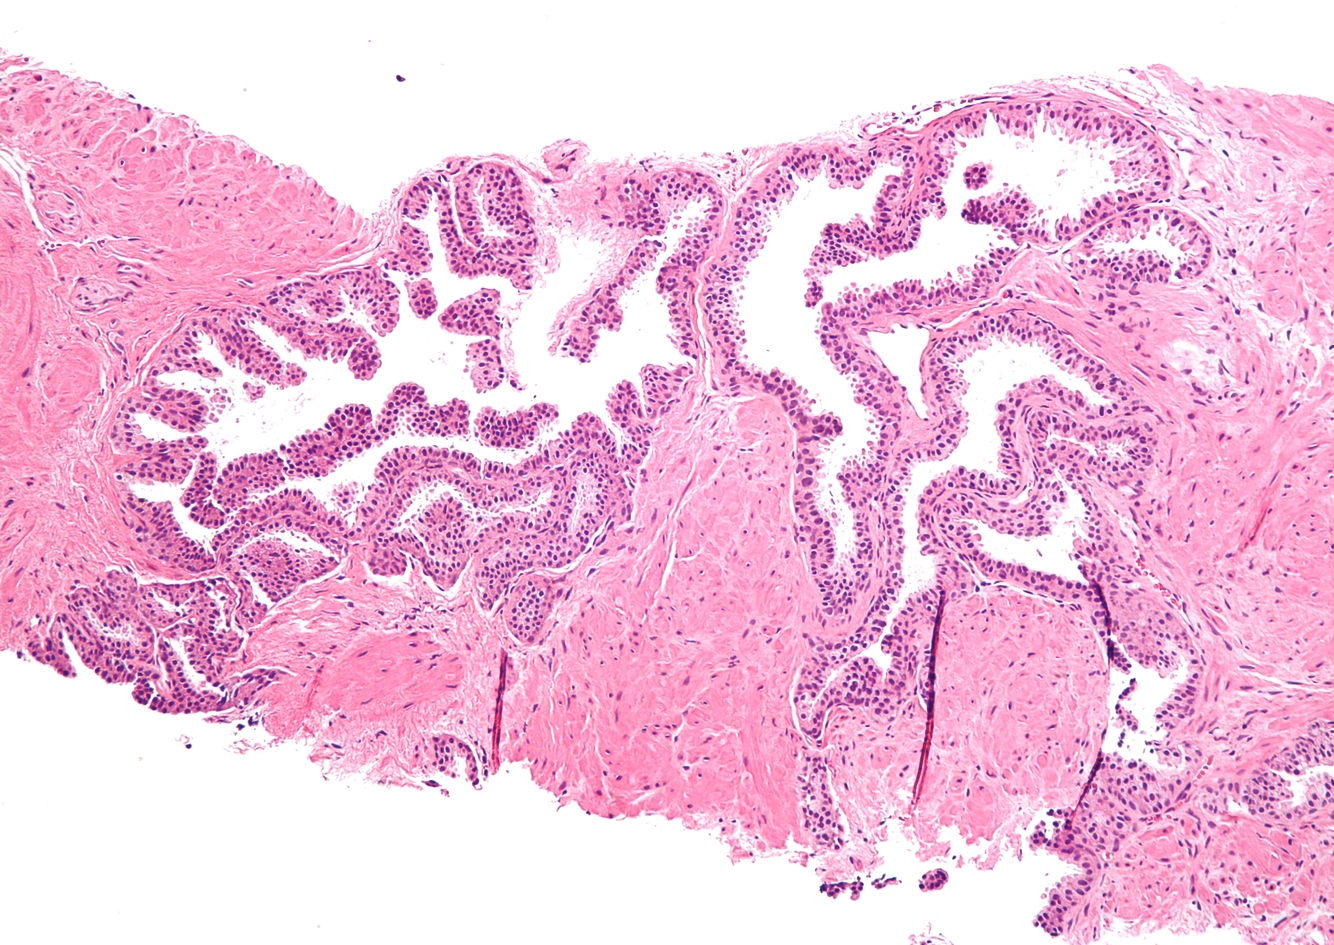

Describe normal prostate histology

double layer of cells: secreatory and basal

flat nuclie, lie at the edge of gland and these basal cells = normal and healthy basally located cells are absent in prostate cancer